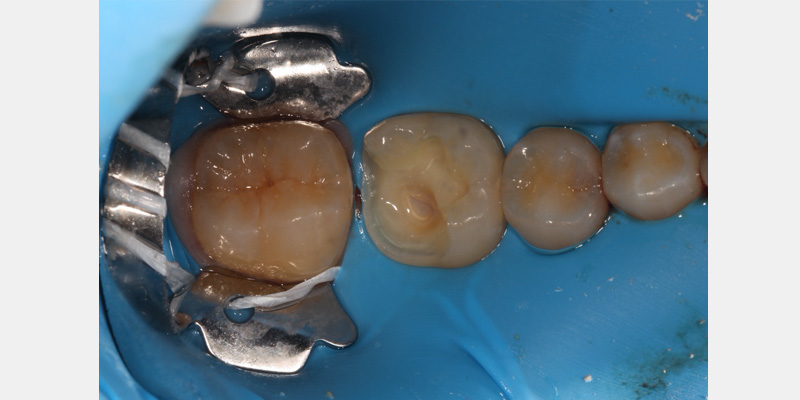

Invariably, leakage may still occur. After the rubber dam is placed, a caulking material can seal any areas that may still have leakage. Various products are available on the market; however, unbonded composite can also be placed and light-cured to act as a caulking agent.

Floss should be used to push the dam through the contact areas of the teeth. After passing through the contact point, the floss can be used to help invert the dam by gently working the floss in to the gingival sulcus. Pulling the floss out buccally, rather than back through the contact point, can help minimize the risk of having the dam dislodge from the tooth.

In some instances, light or open contacts may exist between adjacent teeth, which can present a challenge for securing the dam. Fabricating a floss ligature using a square knot can help secure the dam around the tooth. If this does not work, a thicker material (such as a Wedjet) can be used to hold the dam in place. Alternatively, a corner of the dam can be cut off and used interproximally to secure the dam.